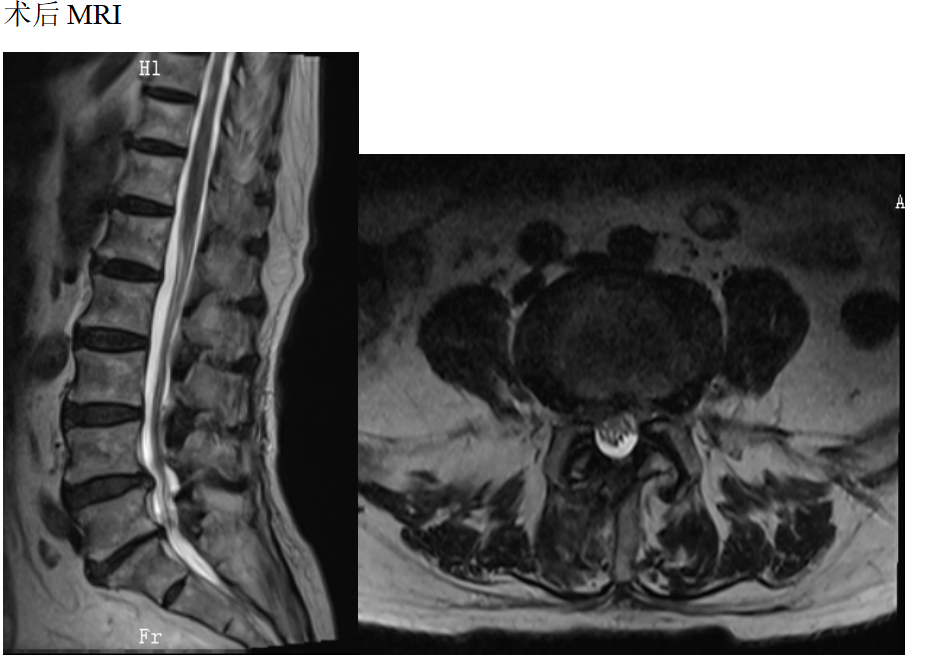

患者女性78岁,主诉:双下肢酸困麻木1年

现病史:1年前出现双下肢酸困麻木,以右侧为主,行走及站立时症状加重,平卧休息稍减轻,未治疗,上述症状持续加重,步行困难,步行能力约100米,为求诊治,现来我院,遂以“腰椎管狭窄症”为诊断收住我科。发病以来,饮食正常,睡眠一般,体力正常,大小便正常。